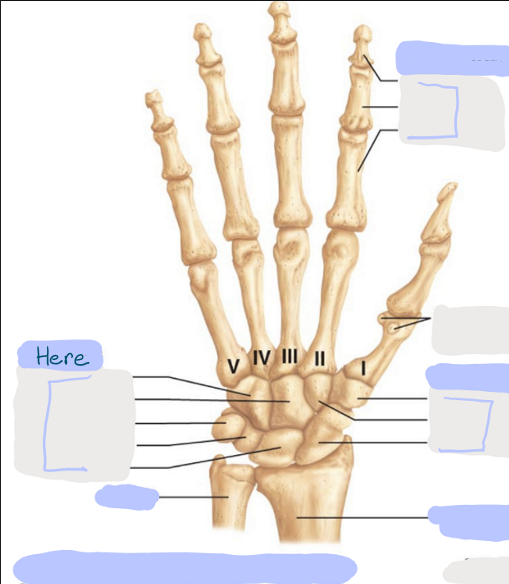

What is this picture of?

Anterior View of the Right Hand

What is here?

Where is the Ulna?

What is here?

Where is the Radius?

What is here?

Where are some of the Carpals?

What is here?

Where are some of the Carpals?

What is here?

Where are the Phalanges?